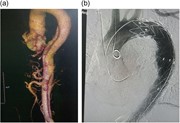

Acute rectal ischaemia following emergency abdominal aortic aneurysm surgery

Frances R. Mosley and others

Journal of Surgical Case Reports, Volume 2016, Issue 10, October 2016, rjw172, https://doi.org/10.1093/jscr/rjw172